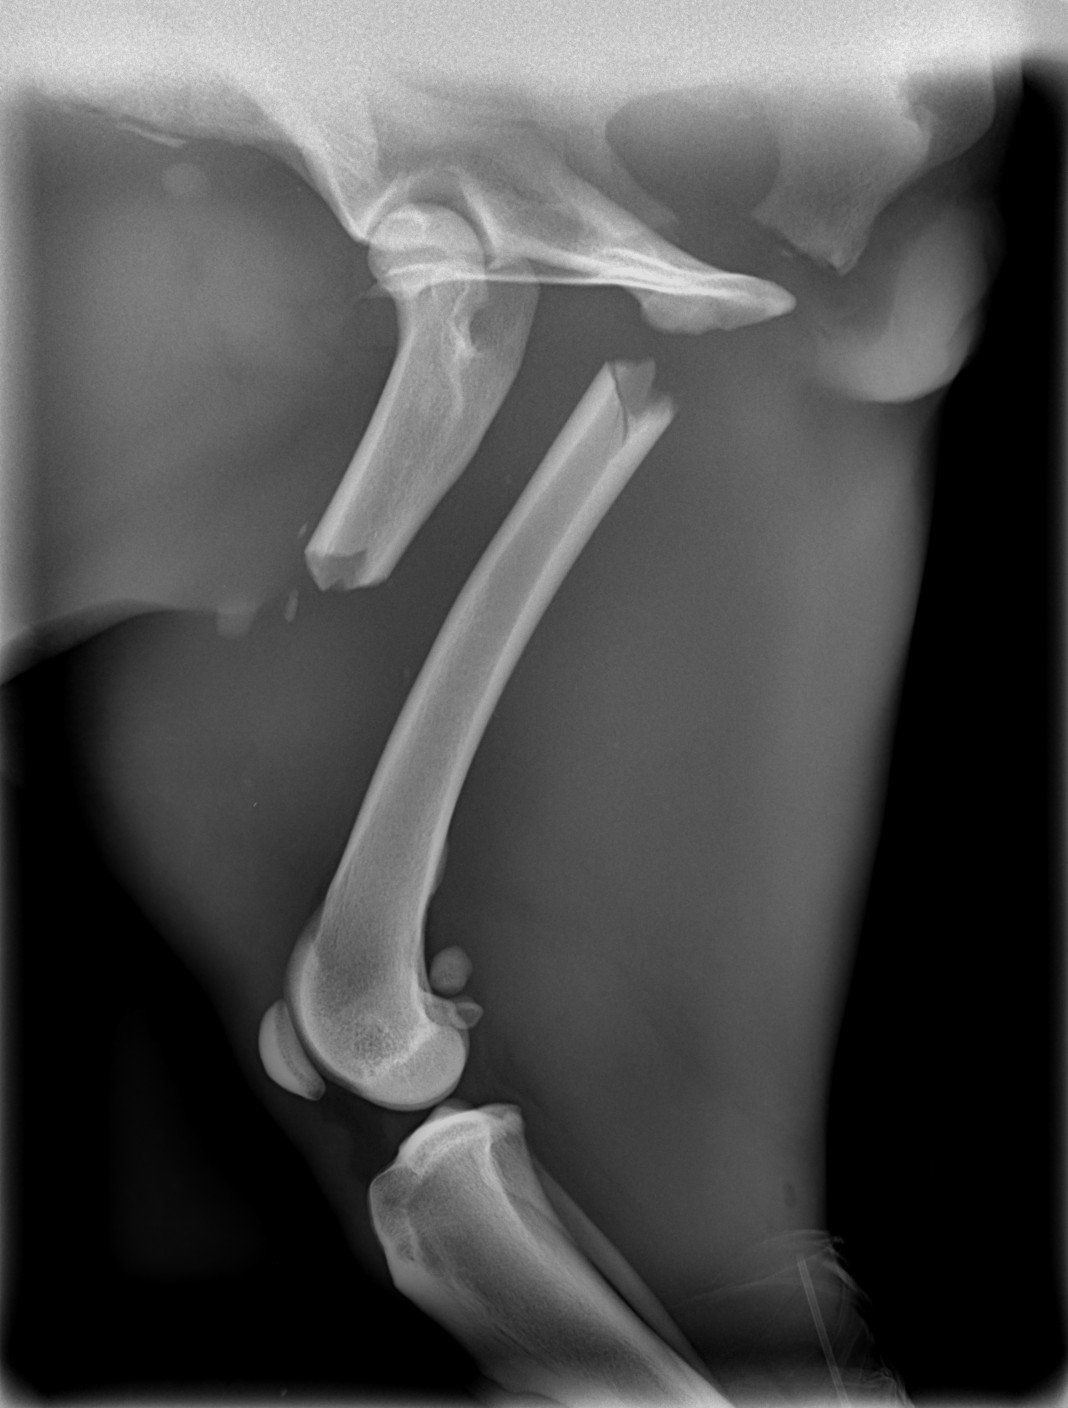

Sushy apareció atropellada en la carretera, de alli la llevaron a la perrera, donde querian sacrificarla, por suerte unas personas la sacaron y nos pidieron ayuda para ella, despues de traerla desde valencia ingreso en un hospital veterinario donde la operaron 3 veces, se paso varias semanas ingresada y cuando por fin salio a una casa de acogida se dio cuenta de que engordo en 3 dias y se le inflamaron las mamas.